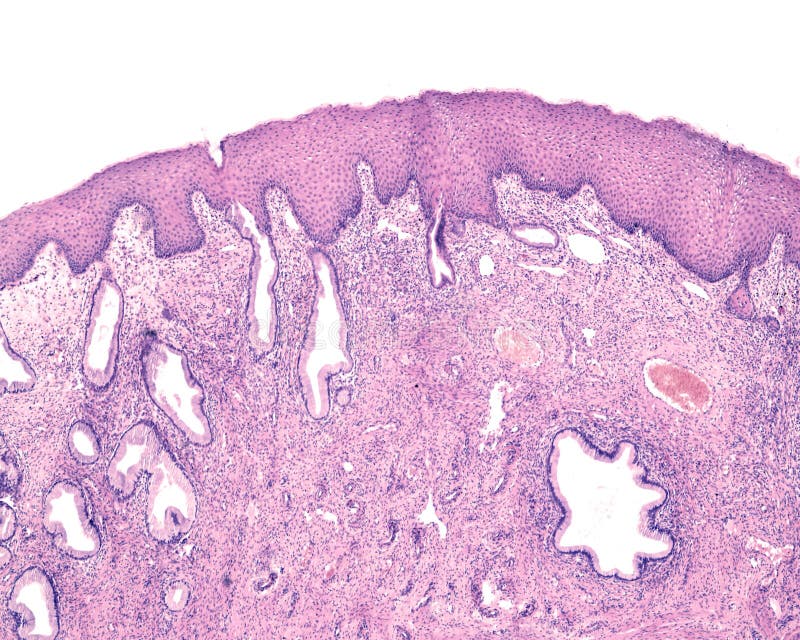

Эндоцервикс метаплазированный эпителий

Эндоцервикс метаплазированный эпителий 114 фотографий